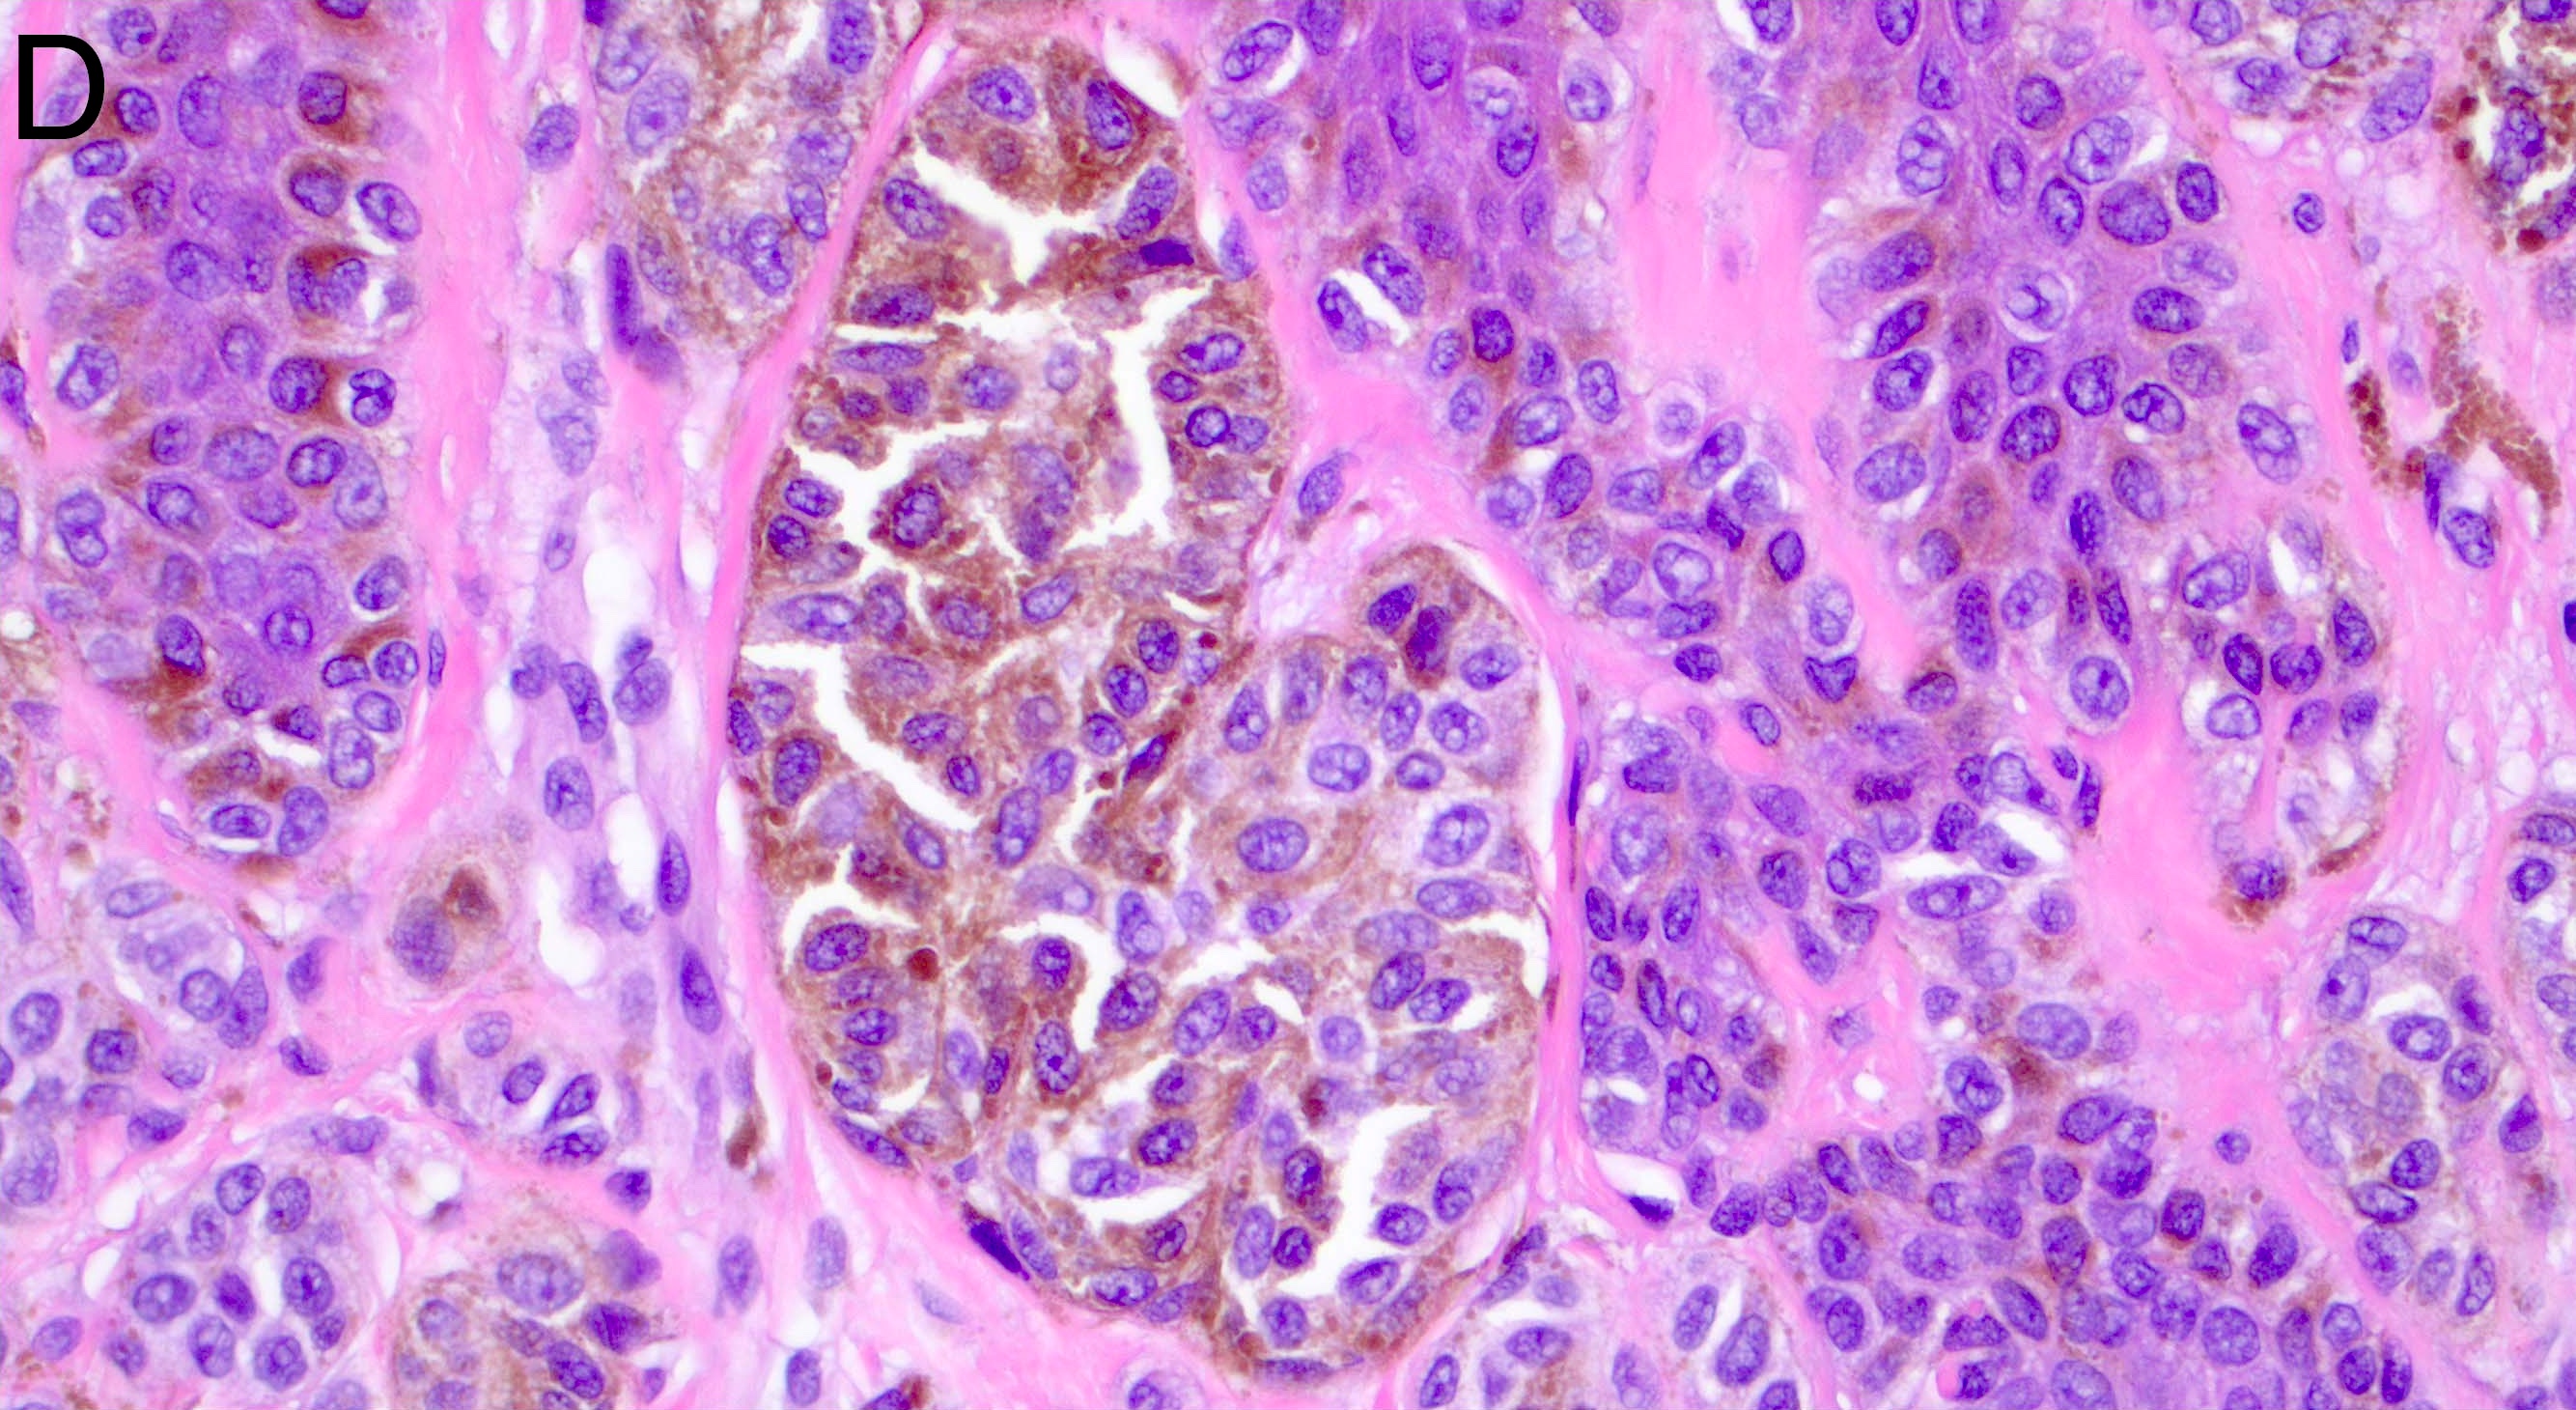

- Melanocytic nevi of the breast (Am J Dermatopathol 2016;38:867):

- May contain large irregular dyshesive nests in close proximity to one another

- Junctional nests may not be centered and can be placed within inter-rete spaces and along sides of rete

- Nests may have variable pigmentation (results in globules seen on dermoscopic exam)

- Nests may have prominent horizontal streaming resulting in rete blunting or epidermal effacement

- Cytologic atypia is common

- Maturation with melanocyte descent should be retained

Microscopic (histologic) images